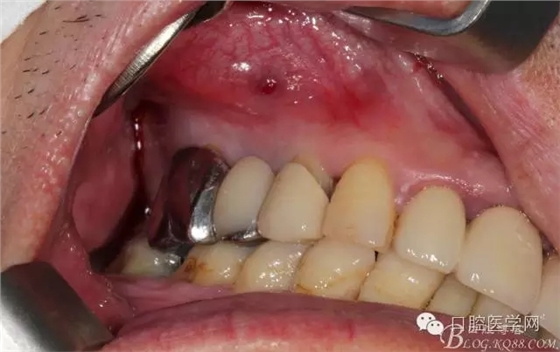

牙周治療以后過了段時(shí)間我們開始拔牙種牙,上圖是牙周治療以后開始種牙的口內(nèi)照片,效果還是有的。